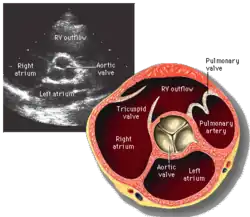

Evaluación

La evaluación del funcionamiento de la válvula aórtica puede hacerse de varias formas. La auscultación con un estetoscopio es rápida y fácil. La ecocardiografía transtorácica es una de las pruebas más útiles, puede cuantificar el grado de estenosis e insuficiencia y es posible determinar el grado de disfunción de la válvula. Otras pruebas menos empleadas son la ecocardiografía transesofágica, la resonancia magnética nuclear y la Tomografía axial computarizada.

La cuantificación de la velocidad máxima a través de la válvula, y el área de apertura, la existencia de calcificación, la morfología (tricúspide, bicúspide, unicúspide) y el tamaño de la válvula (anular, senos, unión sinotubular) son parámetros comunes al evaluar la válvula aórtica.